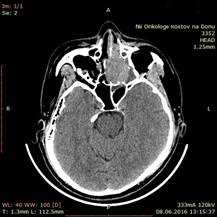

Больная З., 1948 года рождения, поступила в отделение ОГШ ФГБУ «РНИОИ» МЗ РФ 14.06.2016 г. с жалобами на затрудненное носовое дыхание слева, головные боли. При осмотре - лимфатические узлы шеи не увеличены, носовое дыхание через левую половину носа затруднено. Пальпаторно - костные структуры лицевого скелета не разрушены. При передней риноскопии - опухоль не определяется. СРКТ от 08.06.2016 г.: «Слева в области ячеек решетчатого лабиринта определяется мягкотканое образование 42х51 мм с прорастанием в верхнечелюстную и основную пазуху, полость носа (рис. 1). Легочная ткань без очагов. Патологических объемных образований в брюшной полости и полости малого таза не выявлено».

Рис. 1. СРКТ придаточных пазух носа: слева в области ячеек решетчатого лабиринта определяется мягкотканое образование 42х51 мм с прорастанием в верхнечелюстную и основную пазуху, полость носа